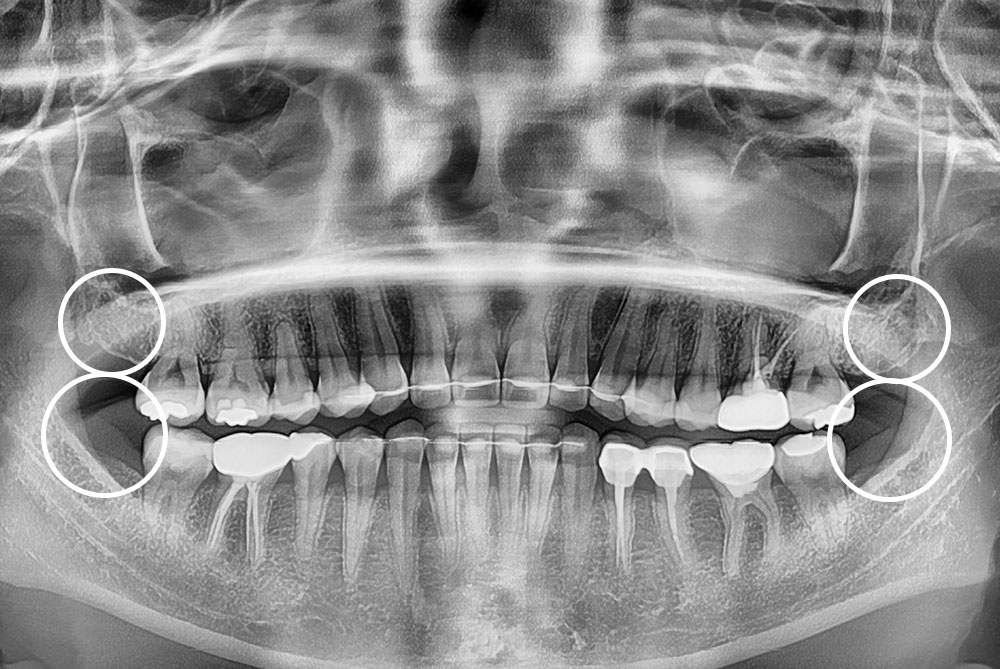

[사랑니] 매복 사랑니 발치

치료후 : 2022-08-24

세종치과는 구강악안면외과학 박사이신 원장님이 발치하는 치과입니다.